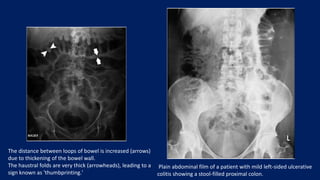

IMAGING STUDIES

• ABDOMINAL X-RAYS

• Assessing for perforation of the viscus and toxic megacolon

• Features of active inflammation include colonic air–fluid levels or loss of

colonic haustration

• In the presence of severe disease, the colon may exhibit an irregular, nodular

contour with mucosal islands separated by severely inflamed mucosa

• Lastly, AXRs may suggest the extent of disease, as an inflamed colon contains

less stool and absence of stool in the colon suggests pancolitis

The distance between loops of bowel is increased (arrows)

due to thickening of the bowel wall.

The haustral folds are very thick (arrowheads), leading to a

sign known as 'thumbprinting.'

Plain abdominal film of a patient with mild left-sided ulcerative

colitis showing a stool-filled proximal colon.